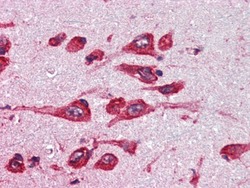

AP22480PU-N IHC

Full details

Method: